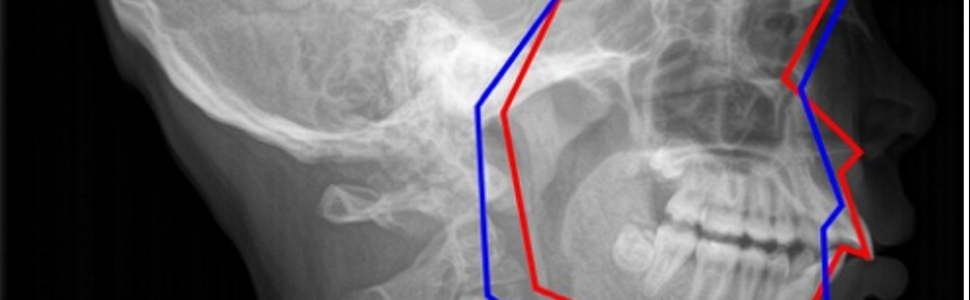

Leczenie nakładkowe metodą Invisalign® Mandibular Advancement wady dotylnej u dzieci.

Opis przypadku 12-letniego chłopca z nasilonym tyłozgryzem leczonym metodą nakładkową. Leczenie trwające 45 tygodni pozwoliło na uzyskanie prawidłowych klas trzonowcowych i kłowych oraz nagryzu poziomego i pionowego.

A case report of a 12-year-old boy with severe Class II malocclusion, treated with aligner method. Treatment lasting 45 weeks allowed to obtain normal molar and canine classes as well as horizontal and vertical overbite.